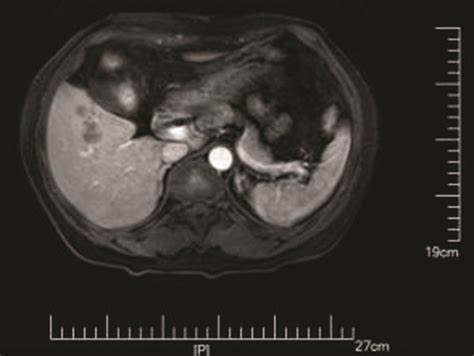

· 深圳某互联网公司:12名员工因长期订购同一品牌轻食,集体感染肝吸虫导致急性肝衰竭。其中3人需进行肝移植,术后病理报告显示肝组织内发现大量华支睾吸虫成虫(体长8-15mm)及钙化虫卵堆积。

· 成虫每日产卵2000-4000枚,虫卵堆积引发胆管机械性扩张(超声显示胆管直径>4mm);

纤维化阶段(3个月后)

· TGF-β1信号通路持续激活,α-SMA阳性肝星状细胞数量增加15倍;

· 肝脏硬度值(LSM)>12.5kPa,胶原沉积面积占肝组织38%以上。